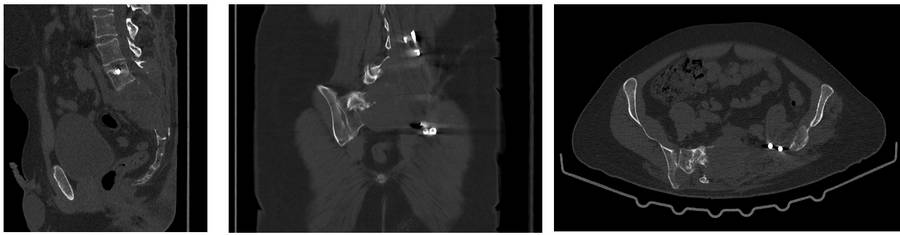

Before the surgery: CT scan shows significant bone damage and tumor recurrence.